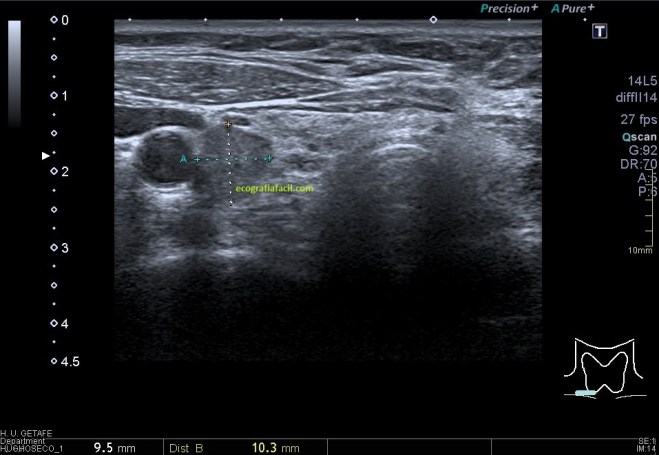

Una vez que hemos encontrado la lesión, es momento de estudiarla detenidamente, su aspecto, tamaño bordes y vascularización son vitales para que la radióloga pueda efectuar un informe.

La imagen 3 y 4 son parte estudian en eje largo y corto las medidas de la lesión en los tres ejes del espacio, en ocasiones, podemos tener más de una lesión. Siempre super atentos si las lesiones son intra o extratesticulares.